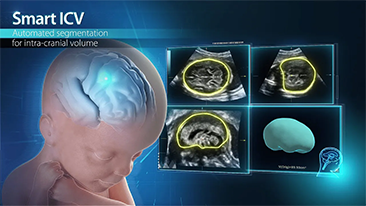

L'ottimizzazione dei flussi di lavoro in ambito ostetrico e ginecologico ├© necessaria per completare grandi volumi di visite di screening per la salute delle donne. Ad esempio, le malformazioni del sistema nervoso centrale (SNC) sono una delle anomalie congenite pi├╣ comuni. A causa di varie circostanze che limitano l'accuratezza delle immagini, come la posizione poco adeguata del feto, l'MSP ├© particolarmente difficile da rilevare tramite l'ecografia 2D. Pertanto, il rilevamento e le misurazioni automatizzate possono migliorare notevolmente l'efficienza della scansione.